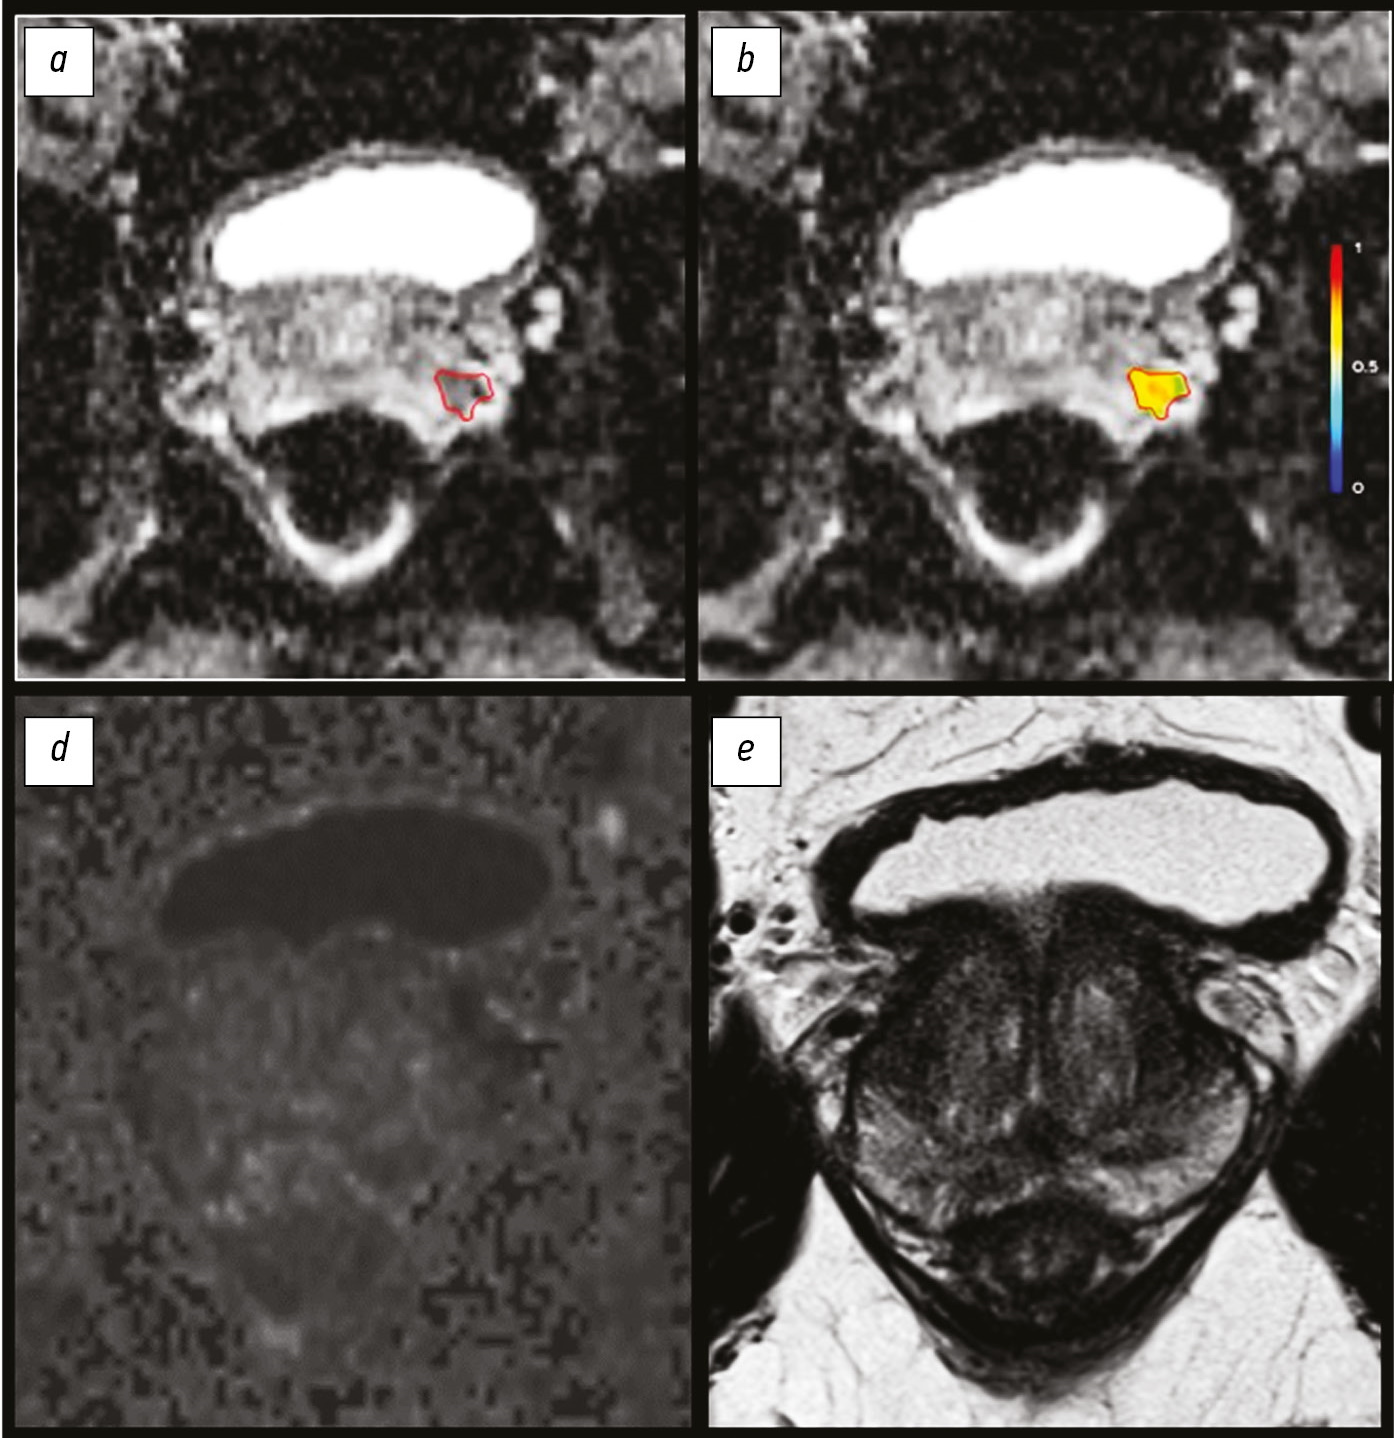

The increasing role of functional visualization modalities for navigation of external beam radiation therapy and brachytherapy in prostate cancer

Brachytherapy is successfully used in the treatment of malignant neoplasms in males and females and rare cases in children, as an independent method (with localized prostate cancer) or adjuvant with remote focal radiation therapy (with cancer of the cervix, anal canal, head and neck, breast, etc.).

The expansion of diagnostic capabilities (the advent of computer and magnetic resonance imaging) due to three-dimensional imaging has given brachytherapy an important technological advantage over other methods. Many options are available for combining brachytherapy with remote radiation or systemic antitumor therapy in the first line, as well as in a single mode for localized tumor recurrence in a previously irradiated area.